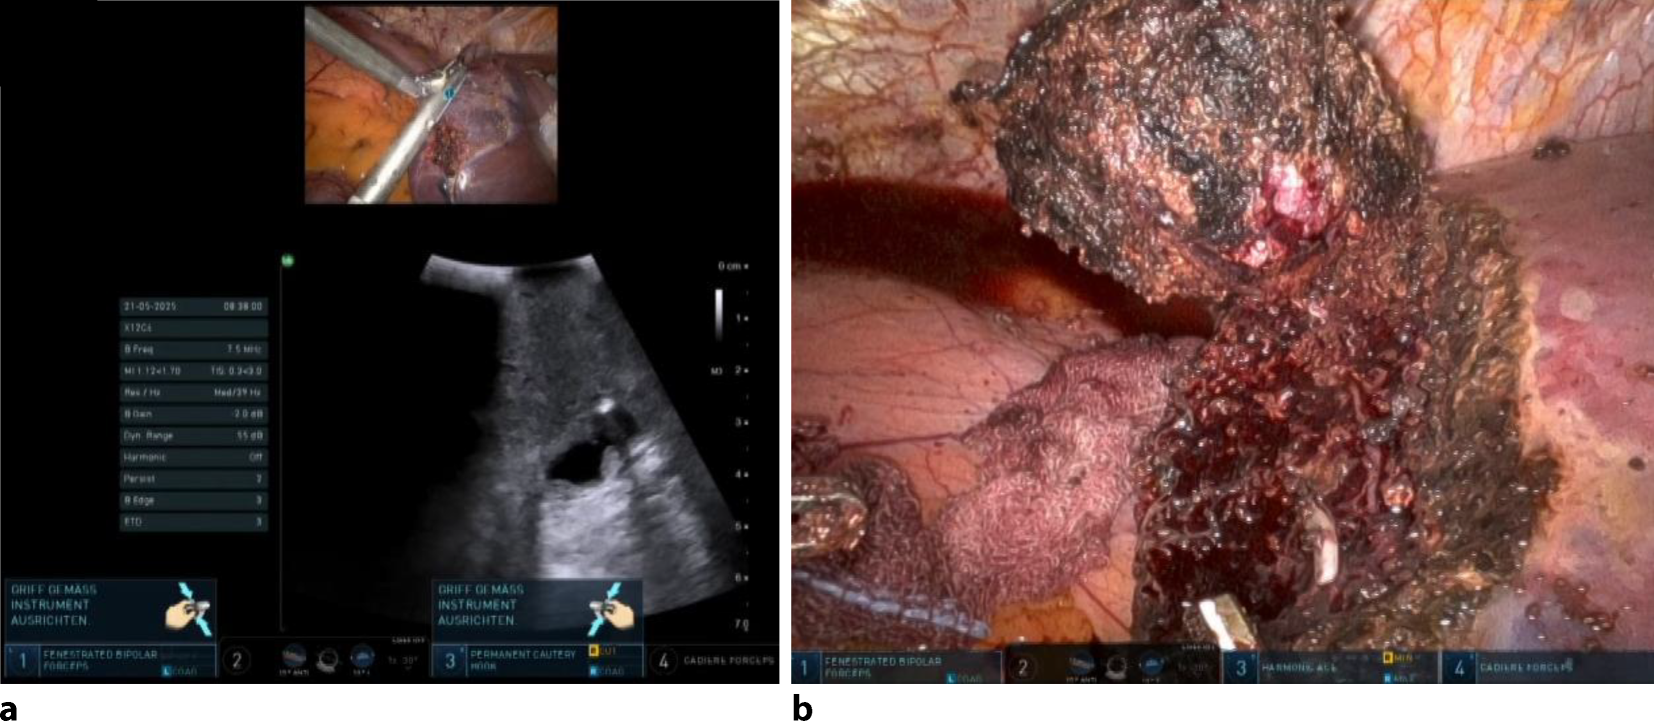

Ein 72-jähriger Patient stellte sich aufgrund von länger bestehenden Stuhlunregelmässigkeiten vor. Die endoskopische Abklärung ergab die Diagnose eines kolorektalen Karzinoms, das primär chirurgisch reseziert wurde. Da keine Hochrisikomerkmale vorlagen, wurde postoperativ auf eine adjuvante Chemotherapie verzichtet. Im Rahmen des onkologischen Follow-up wurde im Verlauf eine solitäre Leberläsion diagnostiziert, die in einem interdisziplinären Tumorboard als resektabel beurteilt wurde. Es erfolgte eine robotisch assistierte atypische Leberresektion und der Patient konnte am dritten Tag entlassen werden (Abb. 3).

Abb. 3

a Intraoperativer Situs mit ultraschallgesteuerter Lokalisation der Metastase. b Situs nach minimal-invasiver Resektion